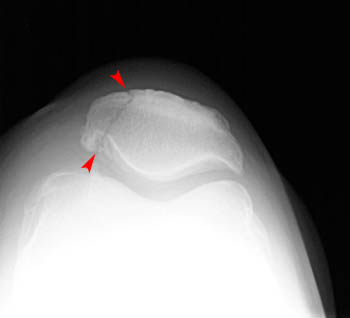

Sunrise view | ||

Fractures of the patella can be confused with bipartite or multipartite patella. The radiographs below

show bipartite patella. Compare the images below with those shown above. Notice that the fractured

patella has pieces that fit together like a jigsaw puzzle. The bipartite or multipartite patella has

pieces with more rounded margins that do not fit together. | ||